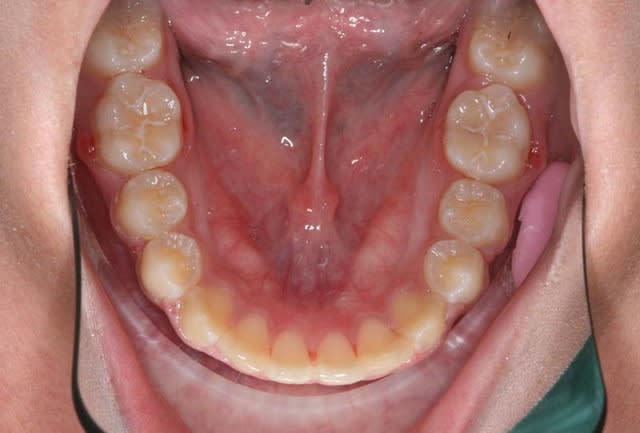

C’est un cas que j’ai traité en deux temps, interception, période d’interruption, fin de TTT.

ce n’est pas un cas trop difficile, aussi j’ai assez peu de photos

Avant TTT.

à suivre Bjc.

c'est le mm. patiente

la coloration des dents est assez remarquable

P.S.: j'avais à l'époque un Fuji mono-objectif

les photos de la contention ont été prises avec un Canon 1000 objectif Macro

les couleurs ne sont pas tout à fait les mm.

mais les dents ont gardé la mm. forme et les taches sont reconnaissables